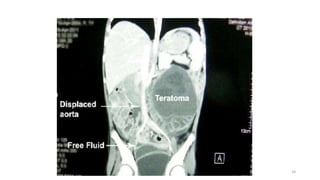

Teratoma.

• Germ cell tumor

• Less than 10% of teratomas

are found in the retroperitoneum.

• The third most common tumor in the retroperitoneum in children, after

neuroblastoma and Wilms tumor

• More common in females, with a bimodal age distribution (<6

months and early adulthood).

• Mature teratoma (dermoid cyst) contains well-differentiated tissues from

at least two germ cell layers.

• Mature teratomas are predominantly cystic.

• Calcification (toothlike or well defined) and fat can be seen in 56% and

93% of cases, respectively 33